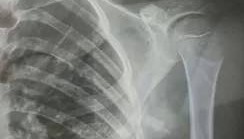

赤峰市教育局介入,家长称:孩子拨弄开关被另一班班主任打伤

10月23日,内蒙古赤峰市宁城县苏木皋小学一学生被老师打伤致锁骨骨折。10月31日,家长贾女士给生...